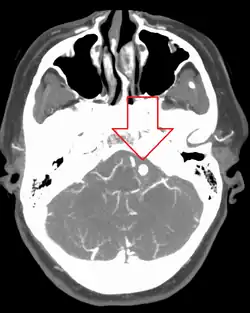

Diagnosis of a ruptured cerebral aneurysm is commonly made by finding signs of subarachnoid hemorrhage on a computed tomography (CT) scan. If the CT scan is negative but a ruptured aneurysm is still suspected based on clinical findings, a lumbar puncture can be performed to detect blood in the cerebrospinal fluid. Computed tomography angiography (CTA) is an alternative to traditional angiography and can be performed without the need for arterial catheterization. This test combines a regular CT scan with a contrast dye injected into a vein. Once the dye is injected into a vein, it travels to the cerebral arteries, and images are created using a CT scan. These images show exactly how blood flows into the brain arteries.[39]